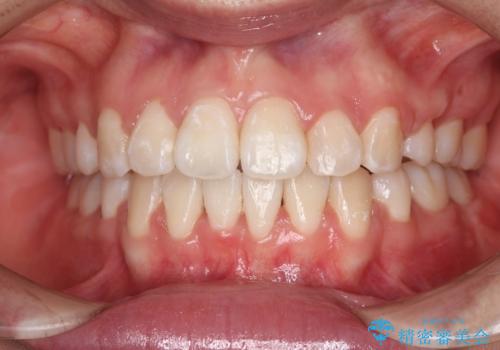

抜歯矯正をして口元を下げたことで、口元が下がりEラインが大変綺麗になりました。

矯正期間も1年9ヶ月と比較的短期間で終了することができました。